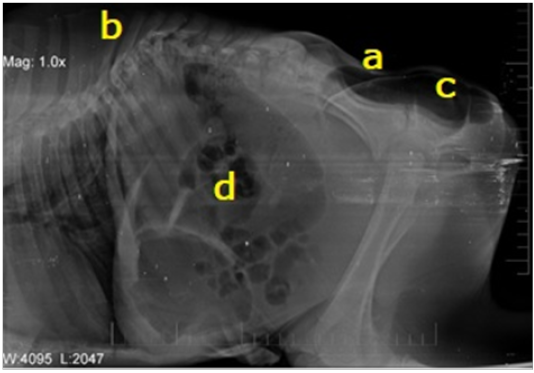

Right lateral abdominal radiograph showing (a) Complete absence of sacral and coccygeal vertebrae. (b) Malformation of thoracic and lumbar vertebrae. (c) Enlarged, gas and fecal matter filled rectum at the region of coccygeal vertebrae. (d) Gas-filled dilated intestinal loops